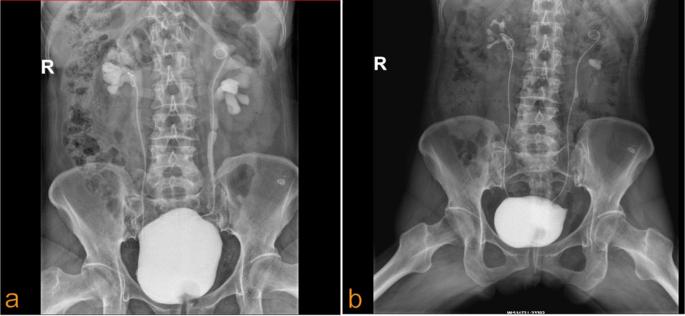

术后第一年和第二年分别进行了输尿管镜检查,结果被归类为Clavien-Dindo 1级。为了防止随后的狭窄,在这些手术中更换了输尿管支架。相应的SCR水平分别为115µmol/L和130µmol/L。肾彩色多普勒超声显示无肾盂积水。逆行膀胱造影显示左输尿管通畅,无造影剂外渗(图4a,b)。

图4 a术后1年膀胱逆行造影检查 b术后2年膀胱逆行对比检查